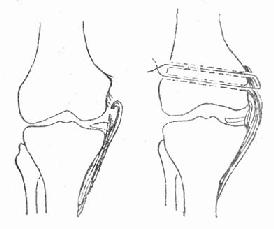

(1)扭傷指間接暴力使肢體和關節周圍的筋膜、肌肉、韌帶過度扭曲、牽拉,引起損傷或撕裂。多發生在關節及關節周圍的組織。

(2)挫傷指直接暴力打擊或衝撞肢體局部,引起該處皮下組織、肌肉、肌腱等損傷。以直接受損部位為主。頸、肩、肘、腕、指間、腕、膝、跺、腰等部位都可引起扭挫傷。其中腰部扭挫傷是最常見的腰部傷筋疾患,多見於青壯年。跌打損傷輕者傷及肌膚,多於短期內痊癒,只用通常膳食治療即可;重者傷筋動骨,創面污染,或出血過多,而致血虛氣衰,甚至傷及內臟,生命垂危,病期較長,則需膳食治療輔佐。